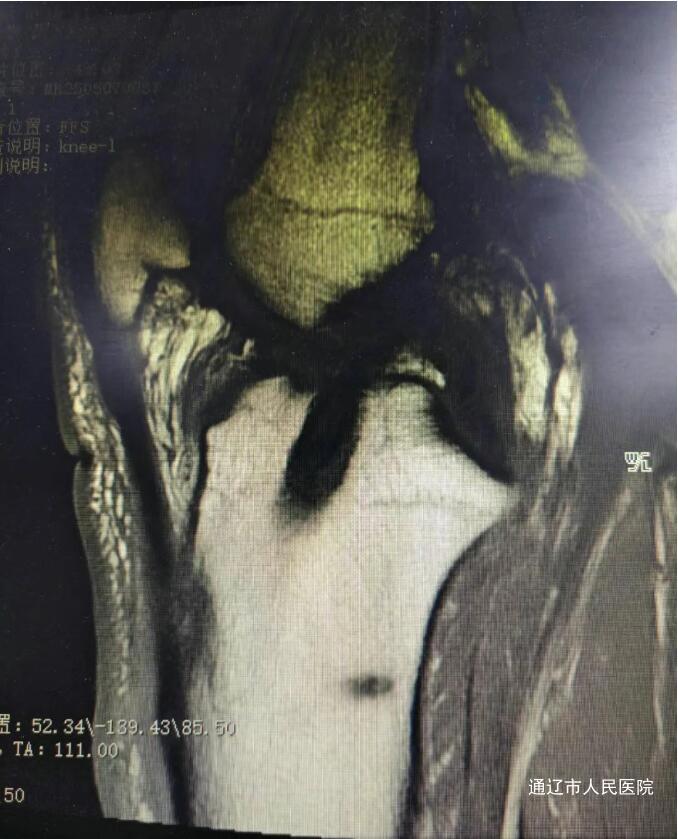

术后